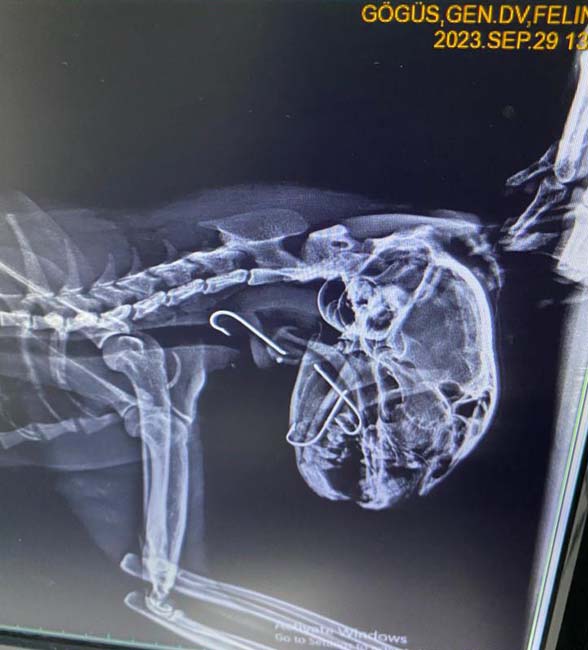

Kilimli ilçesinde bir sokak kedisinin ağzında kanca olduğunu gören vatandaşlar durumu hayvansever Seda Mercan'a iletti. Kediyi bulan Mercan, zabıta ekiplerinden yardım istedi. Veteriner hekime getirilen sokak kedisinin röntgeninde boğazına saplanmış üç tane olta kancası olduğu tespit edildi. Ameliyata alınan kedinin boğazındaki kancalar çıkartıldı. Yaklaşık bir saat süren ameliyatta kancaların derine saplandığı görüldü. Ameliyattan sonra kedi sağlığına kavuşurken veteriner hekim Furkan Alkan, süreci şöyle aktardı:

"Vaka geldiği zaman ağzında salya akıntısı ile geldi. Üç günden beri bu haldeymiş. İlk yaptığımız muayenede kancanın bir kısmını gördük ve hemen röntgeni çektik. Röntgende 3 tane kancanın boğazına takıldığını gördük. Endoskopi yardımıyla 3’ünü birden çıkardık. Üçü de çok derine saplanmıştı. Yarım saat bir saatlik bir operasyonla arkadaş sağlığına kavuştu. Ya balık alırken ya da balıkçılar tarafından atılan balığı kaparken kancayla beraber kaptı. Kancaları yuttu. Oraya saplandığı için de ne ağızda kaldı ne de mideye gitti. 3-4 günden beri enfeksiyonlu ağız akıntısı varmış, kliniğimize gelip tedavisini gördü. 4-5 yaşlarında sokak hayvanı. Bir hayvansever tarafından getirildi. Masraflarını hayvansever karşılıyor."